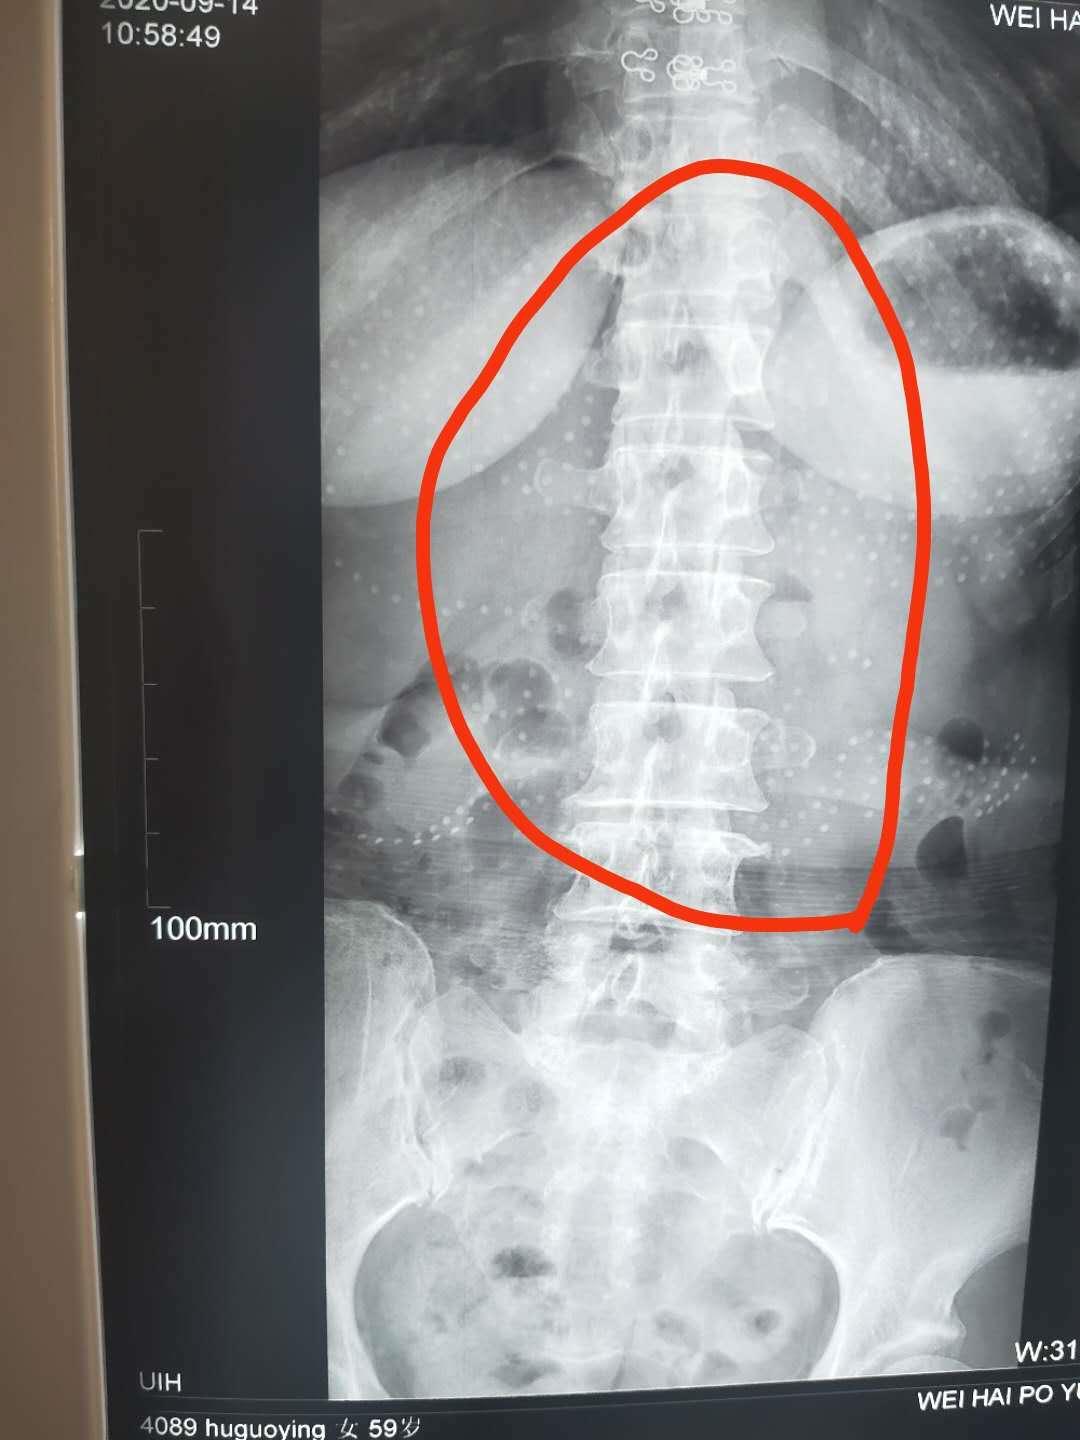

另外一位“腰痛”患者是束着腰围来就诊的,其病史更长,20余年曾因为腰部外伤腰椎骨裂后,反复腰痛发作,翻身转侧困难,稍有过度劳累就会出现腰痛加重,病人自述是就像是一种”掉腰“的感觉,没有办法,只能经常带着腰围固定住腰部,仔细查体并行相应辅助检查,查体发现:患者双下肢左短右长,腰椎曲度变直,脊椎腰段压痛叩击痛明显,腰椎左侧最长肌、髂肋肌、腰方肌肌腹及附着点明显紧张压痛,X片检查提示,患者存在腰椎椎体旋转,综合分析,该患者治疗的重点不同于上位患者,病位在椎周而不在椎管内,今日行小针刀整体松解术暨脊柱小关节紊乱整复术,术后,患者诸证若失,接着我们需要做的就是针灸,中药独活寄生汤内服,中药外敷等巩固性治疗了。